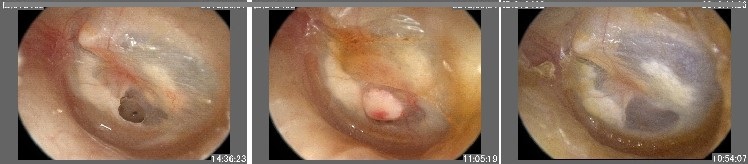

当院では、鼓膜用レーザーとテルダーミスという人工皮膚材を用いて、鼓膜穿孔閉鎖術を行っています。短時間に行える低侵襲の方法で、手術というより処置といった方が適切かもしれません。 手術は、診察椅子に座ったまま行い、麻酔開始から手術終了まで20分程度です。

- (3) 最後に、鼓膜穿孔を人工皮膚剤・テルダーミスで塞いで、終了です。

手術のあと2か月程度で、穿孔縁から鼓膜が伸びて、穿孔が次第に小さくなり塞がっていきます。その間、数回通院して頂きます。1回目の手術で閉鎖しなかった場合も、3回まで手術を繰り返します。2回目以降の手術は処置として手術料金は発生しません。